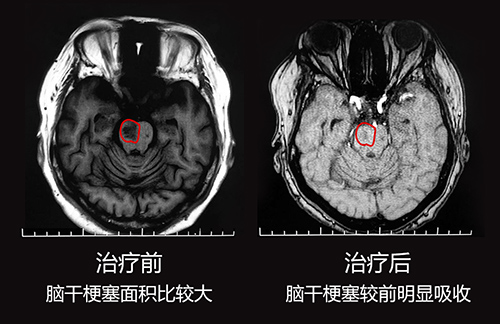

9月19钱阿姨在老伴和儿子的陪伴下就诊于蓝十字脑科医院。神经内科特需专家王玉霞主任详细了解钱阿姨的病症和治疗情况后,完善相关检查,进行了头颅MRI平扫+DWI+MRA,检查结果:1、患者脑干梗塞(急性期);2、双侧大脑半球白质多发腔梗;3、脑白灰疏松;4、MRA脑动脉硬化。

检查结果显示,钱阿姨目前脑干梗塞情况还是比较严重的,王玉霞主任决定先对其进行药物治疗,通过药物治疗可以活血通络,扩张血管,改善微循环,控制和缩小其脑干梗塞面积,之后再结合中医治疗和康复治疗。经过一周有效的治疗后,钱阿姨脑干梗死情况比之前明显好转,病情基本稳定,王玉霞主任告诉钱阿姨接下来主要就是康复治疗问题。